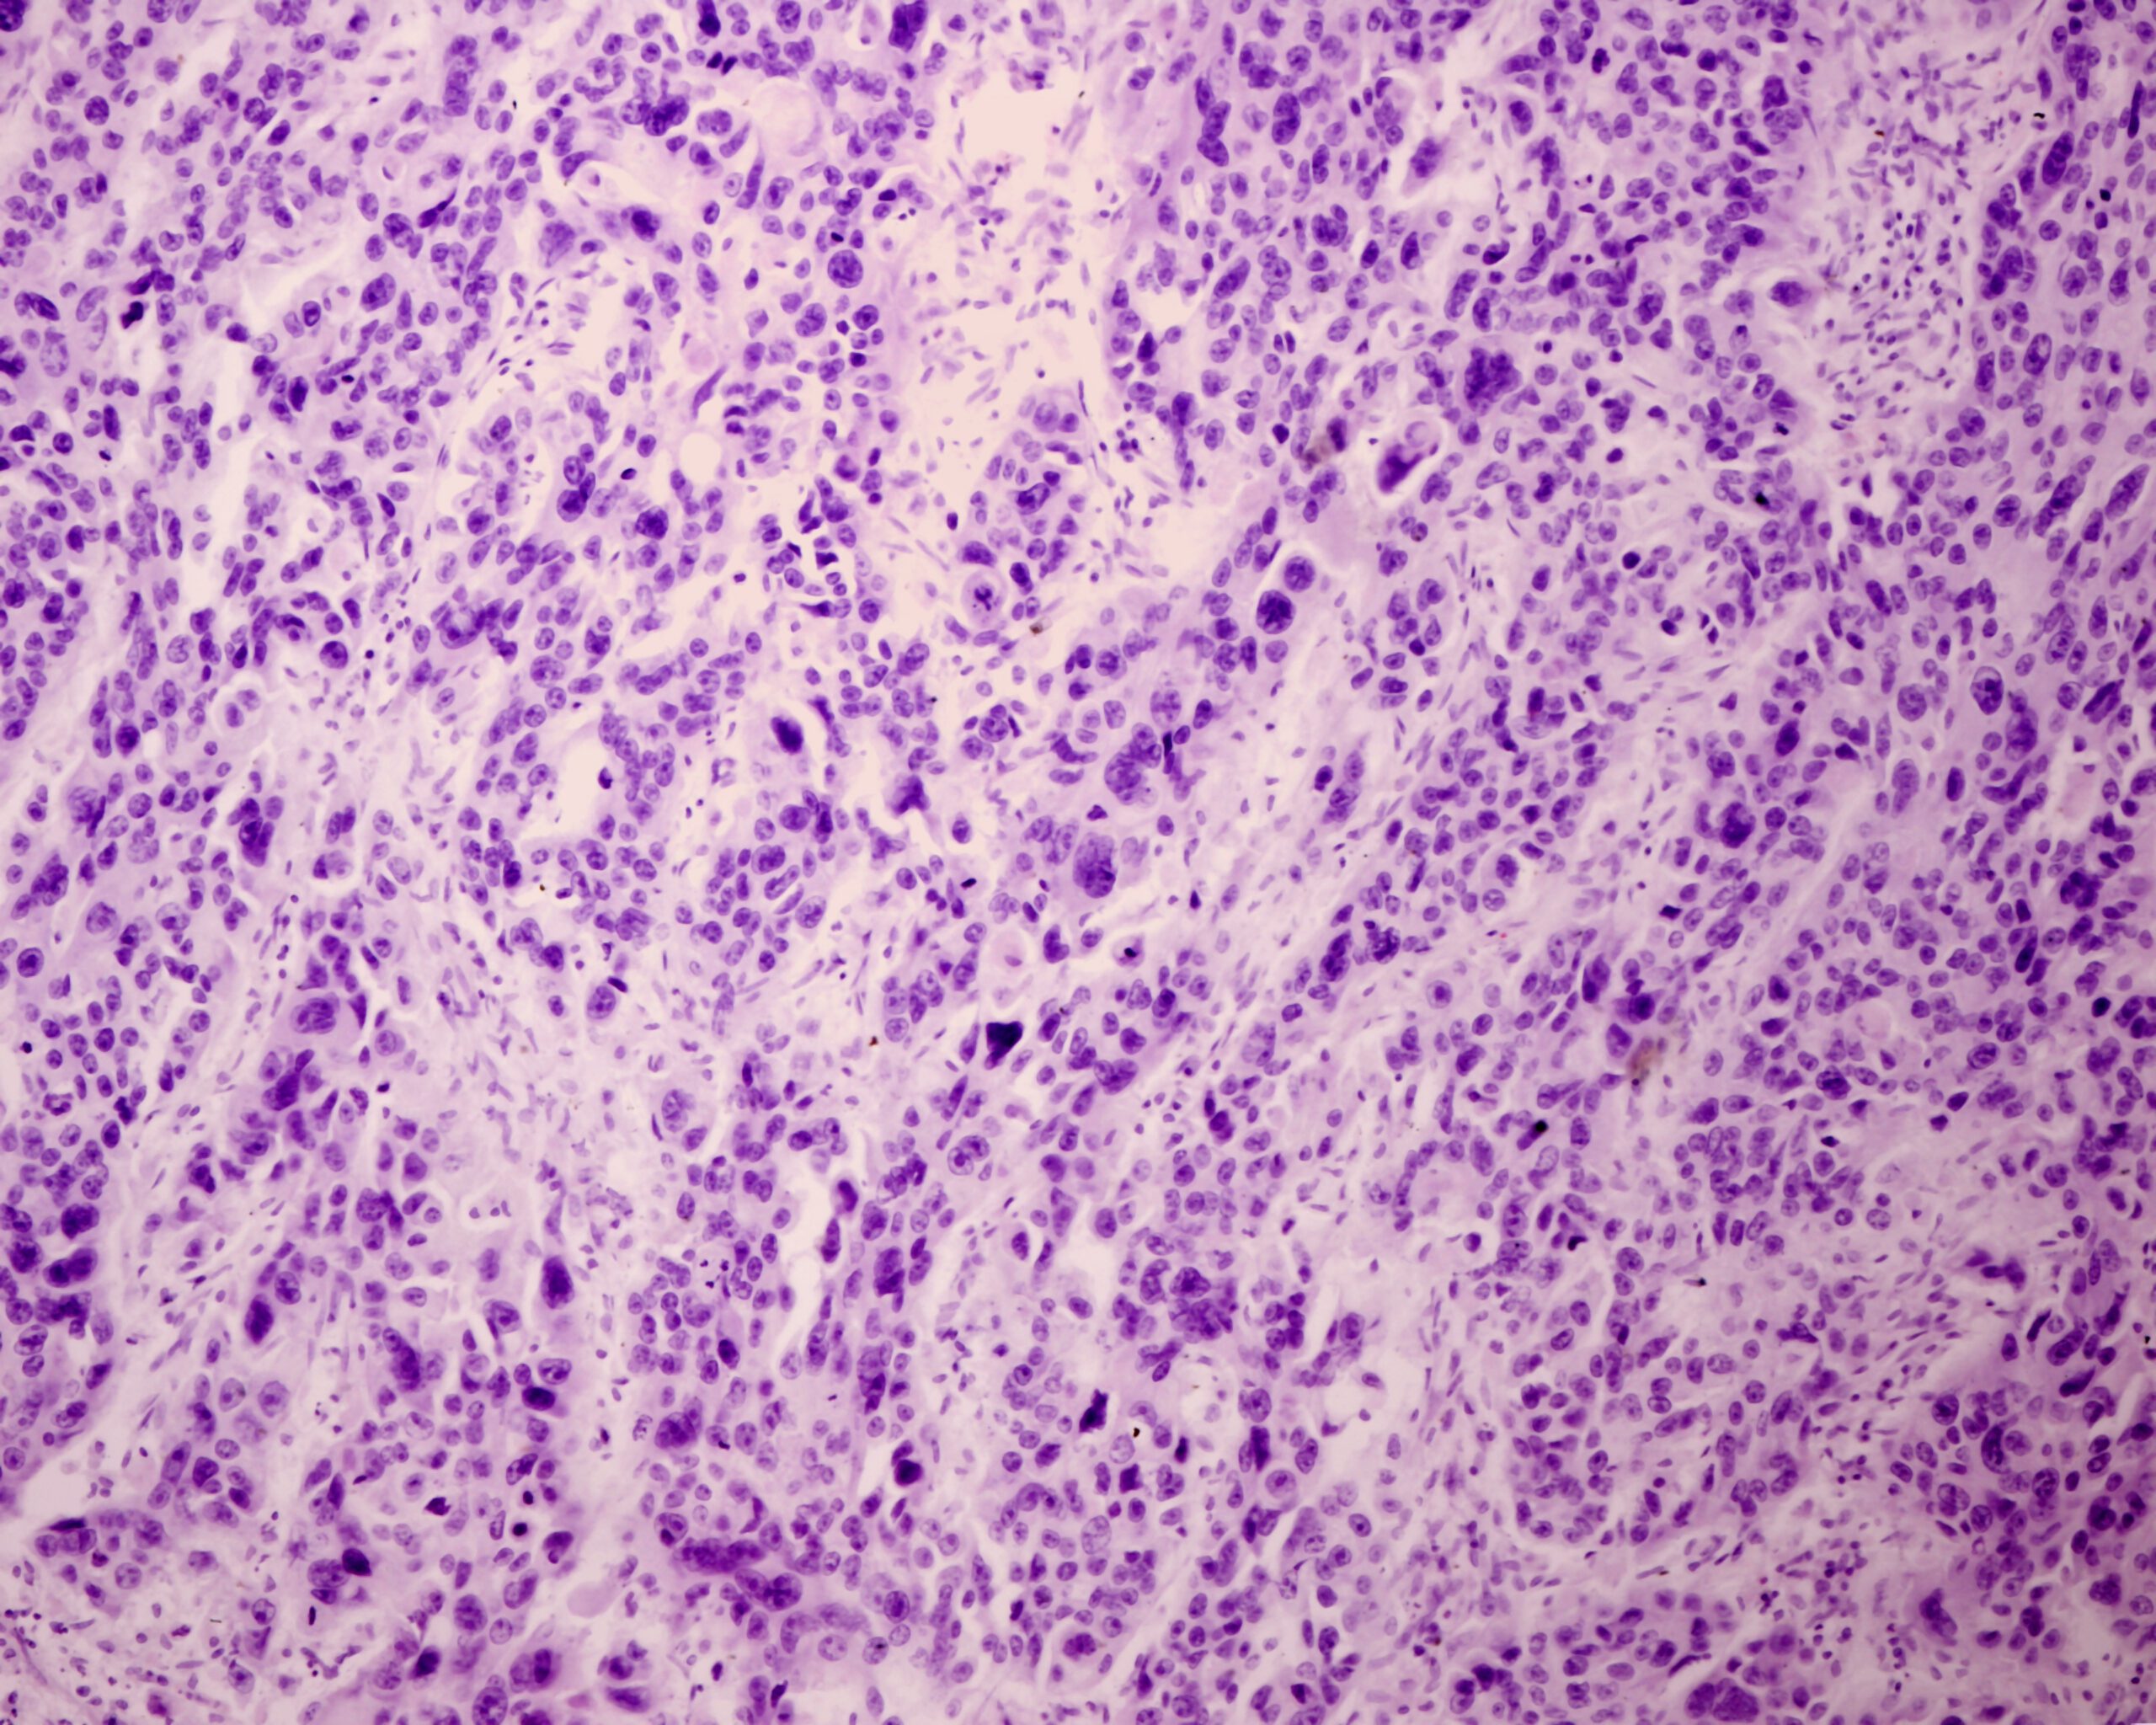

Modeling systemic hematological malignancies requires robust, disseminated disease models and a deep understanding of disease progression. At BioLegacy, we provide definitive efficacy data for your anti-leukemia therapeutic by leveraging well-characterized models to accurately recapitulate human disease. Our expertise in tracking tumor burden in the bone marrow, spleen, and peripheral blood delivers a clear, quantitative assessment of your compound’s therapeutic activity against disseminated cancer.